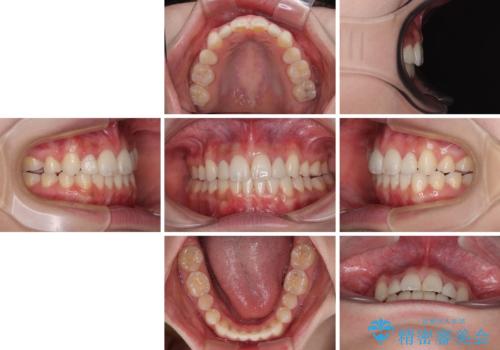

飛び出した前歯 インビザラインを用いた抜歯矯正治療

- 前方に飛び出した前歯を気にして来院された患者様です。

遠方の地元へ転居する予定があるとのことで、インビザラインによる治療を希望されていらっしゃいました。

上下前歯同士の距離が離れているため、上顎左右第一小臼歯2本を抜歯することで前突を改善することとしました。

しかしながら、左右ともに側切歯が矮小歯であるため、矯正治療で矮小歯前後にスペースを作り、矯正治療後にオールセラミッククラウンにて補綴治療を行うこととしました。

治療途中で地元へ転居され、飛行機での通院となったため、治療期間が長くなりましたが、自然で整った口元に仕上げることができました。